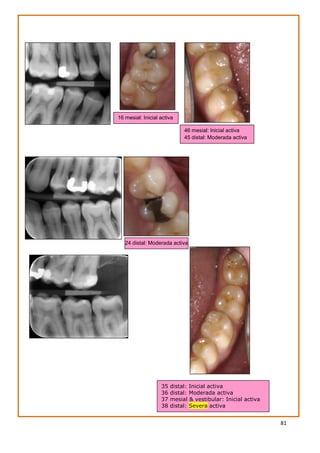

recomendado para niños ≤ 6 años. (SIGN 1---)

67,76

MNO: Sellantes a base

de resina/ionómero de

vidrio (SIGN 1+ / 1---)

65,79

MNO: Sellantes a base de

resina /infiltrantes

(SIGN 2--) 87

MNO: Higiene oral con crema dental fluorada (1000 ppm) cuando